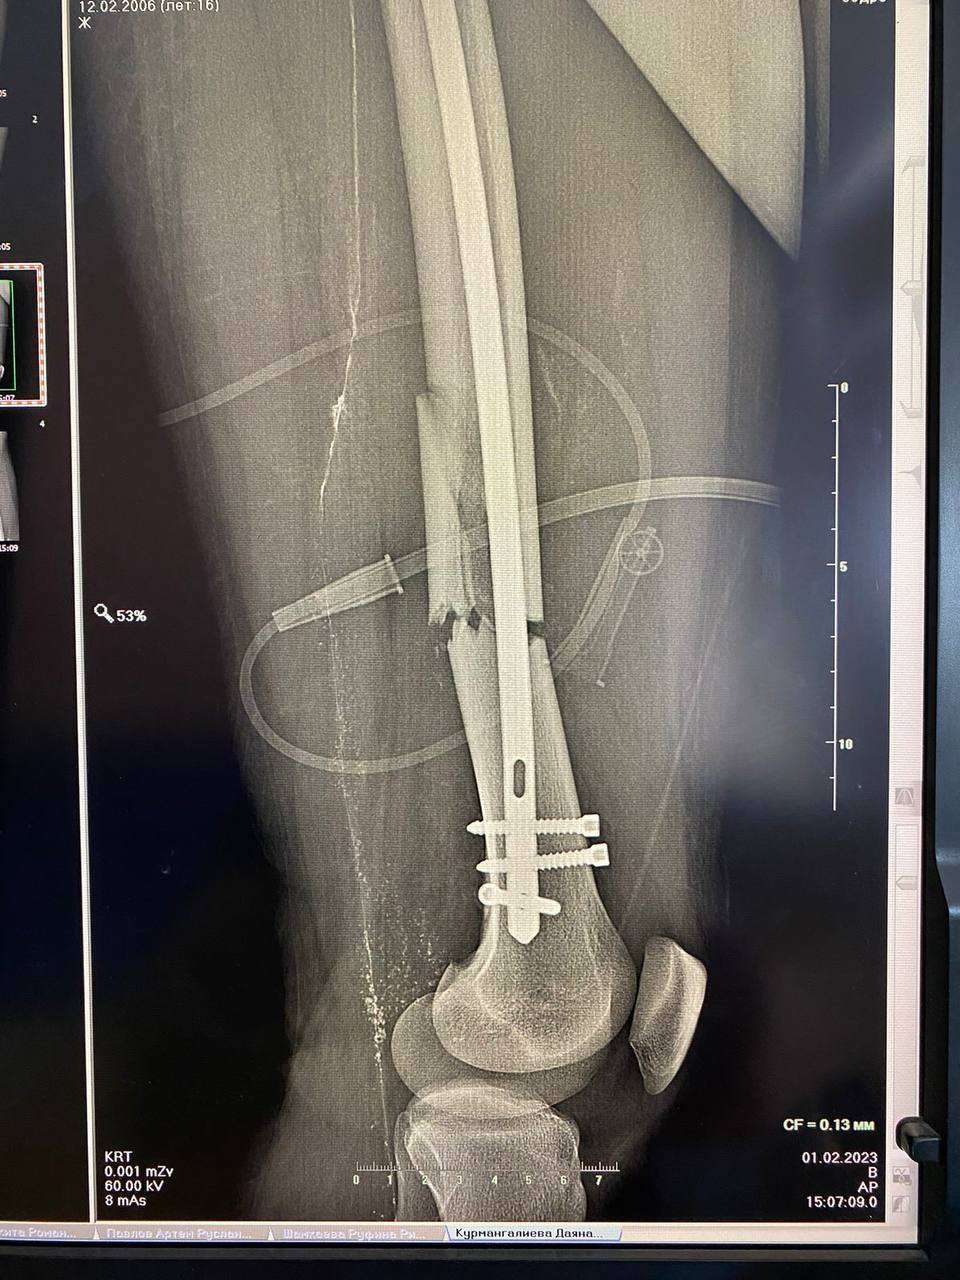

Врачи ОДКБ совместно с хирургами Городской больницы №4 сделали операцию подростку, у которого была сломана левая бедренная кость со смещением отломков.

Врачи ОДКБ совместно с хирургами Городской больницы №4 сделали операцию подростку, у которого была сломана левая бедренная кость со смещением отломков. Источник фото: ОДКБ

Поскольку у медиков 4-й городской больницы большой опыт в проведении подобных операций, было решено их привлечь к работе. Операцию проводил травматолог-ортопед высшей категории Городской больницы №4, к.м.н, доцент, завкафедрой травматологии и ортопедии ОрГМУ Андрей Гурьянов. Ассистентами выступили травматологи ОДКБ Иван Четвериков и Александр Бугаев.

Пациенту провели болокириванный интрамедуллярный стержневой остеосинтез, рассказали в пресс-службе ОДКБ. Спустя два дня после операции подростка вертикализовали при помощи костылей. Болей стало меньше, а отек начал спадать.